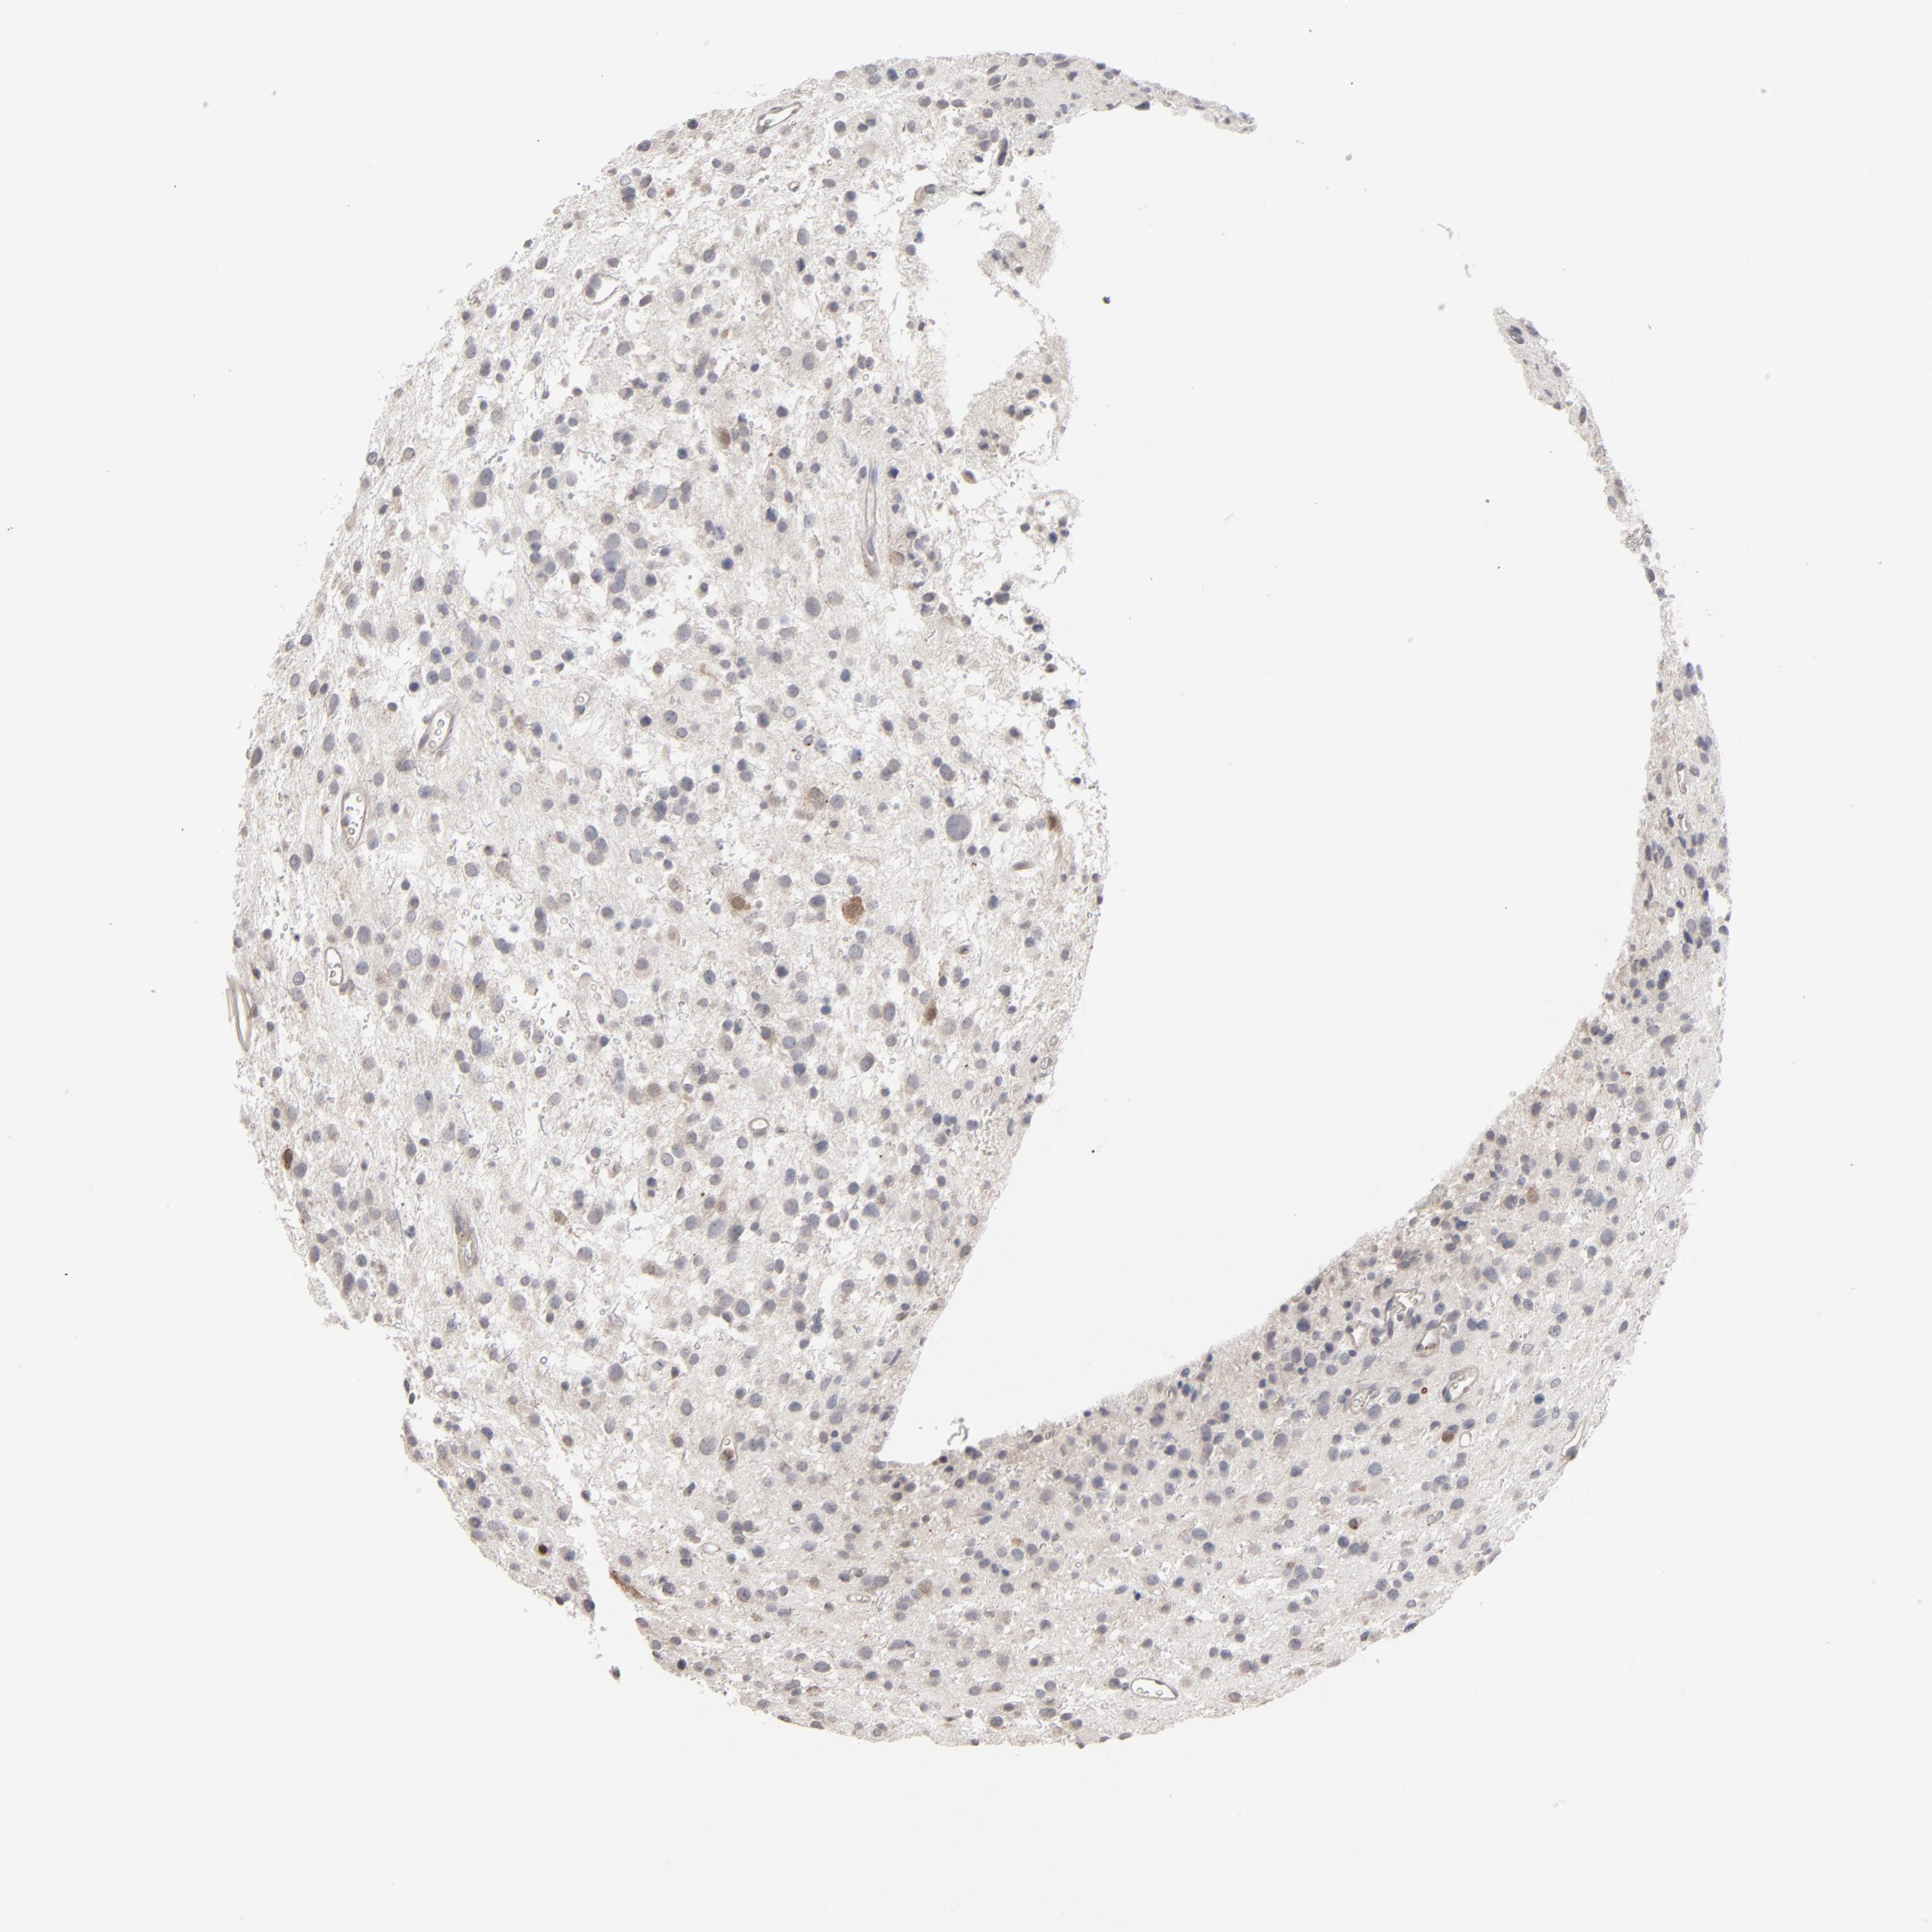

GLIOMA - Protein expressioni

A mouse-over function shows sample information and annotation data. Click on an image to view it in a full screen mode. Samples can be filtered based on level of antibody staining by selecting one or several of the following categories: high, medium, low and not detected. The assay and annotation is described here.

Note that samples used for immunohistochemistry by the Human Protein Atlas do not correspond to samples in the TCGA dataset.

Antibody stainingi

Antibody staining in the annotated cell types in the current human tissue is reported as not detected, low, medium, or high, based on conventional immunohistochemistry profiling in selected tissues. This score is based on the combination of the staining intensity and fraction of stained cells.

Each image is clickable and will lead to virtual microscopy that enables deeper exploration of all samples and also displays staining intensity scores, fraction scores and subcellular localization as well as patient and tissue information for each sample.

Antibody HPA001860

Antibody CAB013108

Staining

High

Medium

Low

Not detected

Intensity

Strong

Moderate

Weak

Negative

Quantity

>75%

75%-25%

<25%

None

Location

Nuclear

Cytoplasmic/membranous

Cytoplasmic/membranous,nuclear

Glioma, malignant, High grade

Glioma, malignant, Low grade